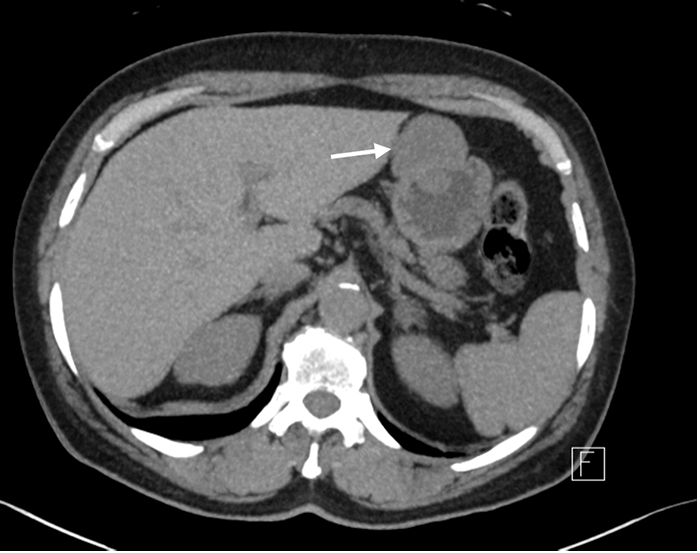

A 62-year-old female with a history of gastroesophageal reflux disease and a 50+ pack year smoking history underwent surveillance chest CT for pulmonary nodules when an incidentally discovered gastric mass was noted. This finding was confirmed with dedicated abdominal and pelvic CT, which demonstrated a 4.1 × 4.3 cm partially exophytic mass on the lesser curvature of the stomach, roughly 9 cm from the gastroesophageal junction (Figure 1). The mass was well circumscribed with no invasion into adjacent structures. Based on the location of the mass and its homogenous appearance on imaging, our initial diagnosis was that of a gastrointestinal stromal tumor (GIST). Apart from the patient’s long-standing reflux disease, she denied any other gastric symptoms.

Figure 1. Dedicated CT Scan of Abdomen and Pelvis After Incidental Discovery of Gastric Mass. Published With Permission